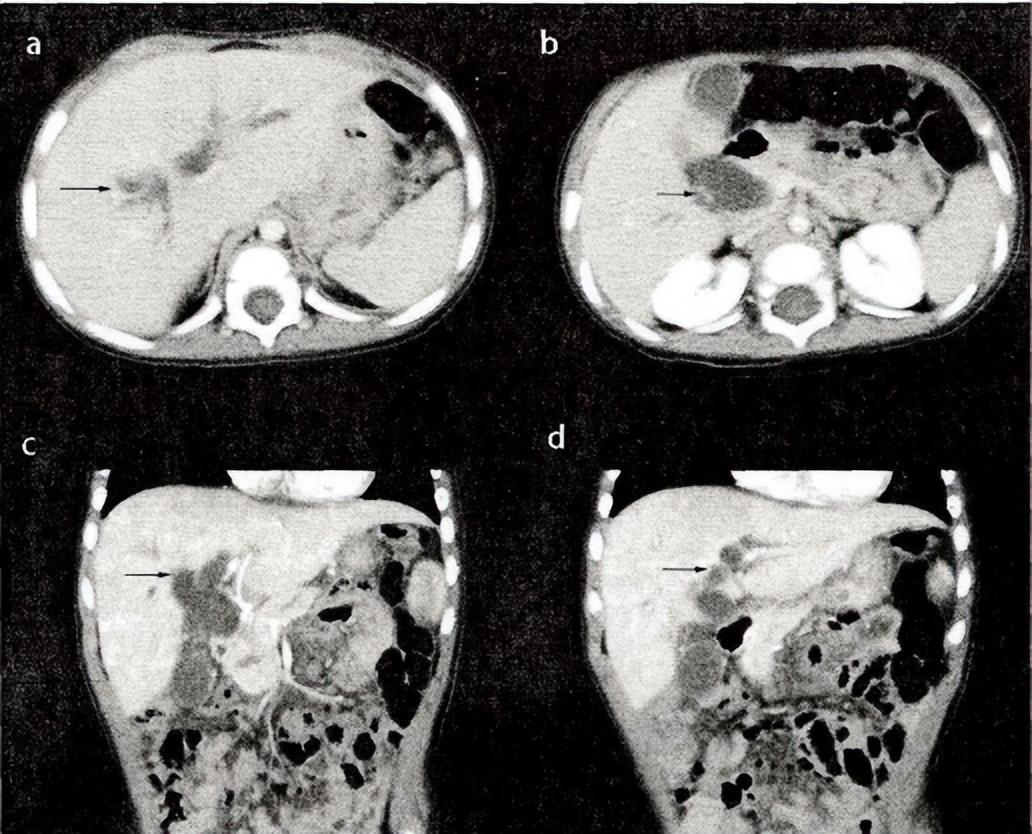

伴有iVa型CBD的PBM患者腹部增强CT图像(一:表现为肝内外胆管多发扩张)。a、B.横断位原始图像;C、D.冠状位重建图像。